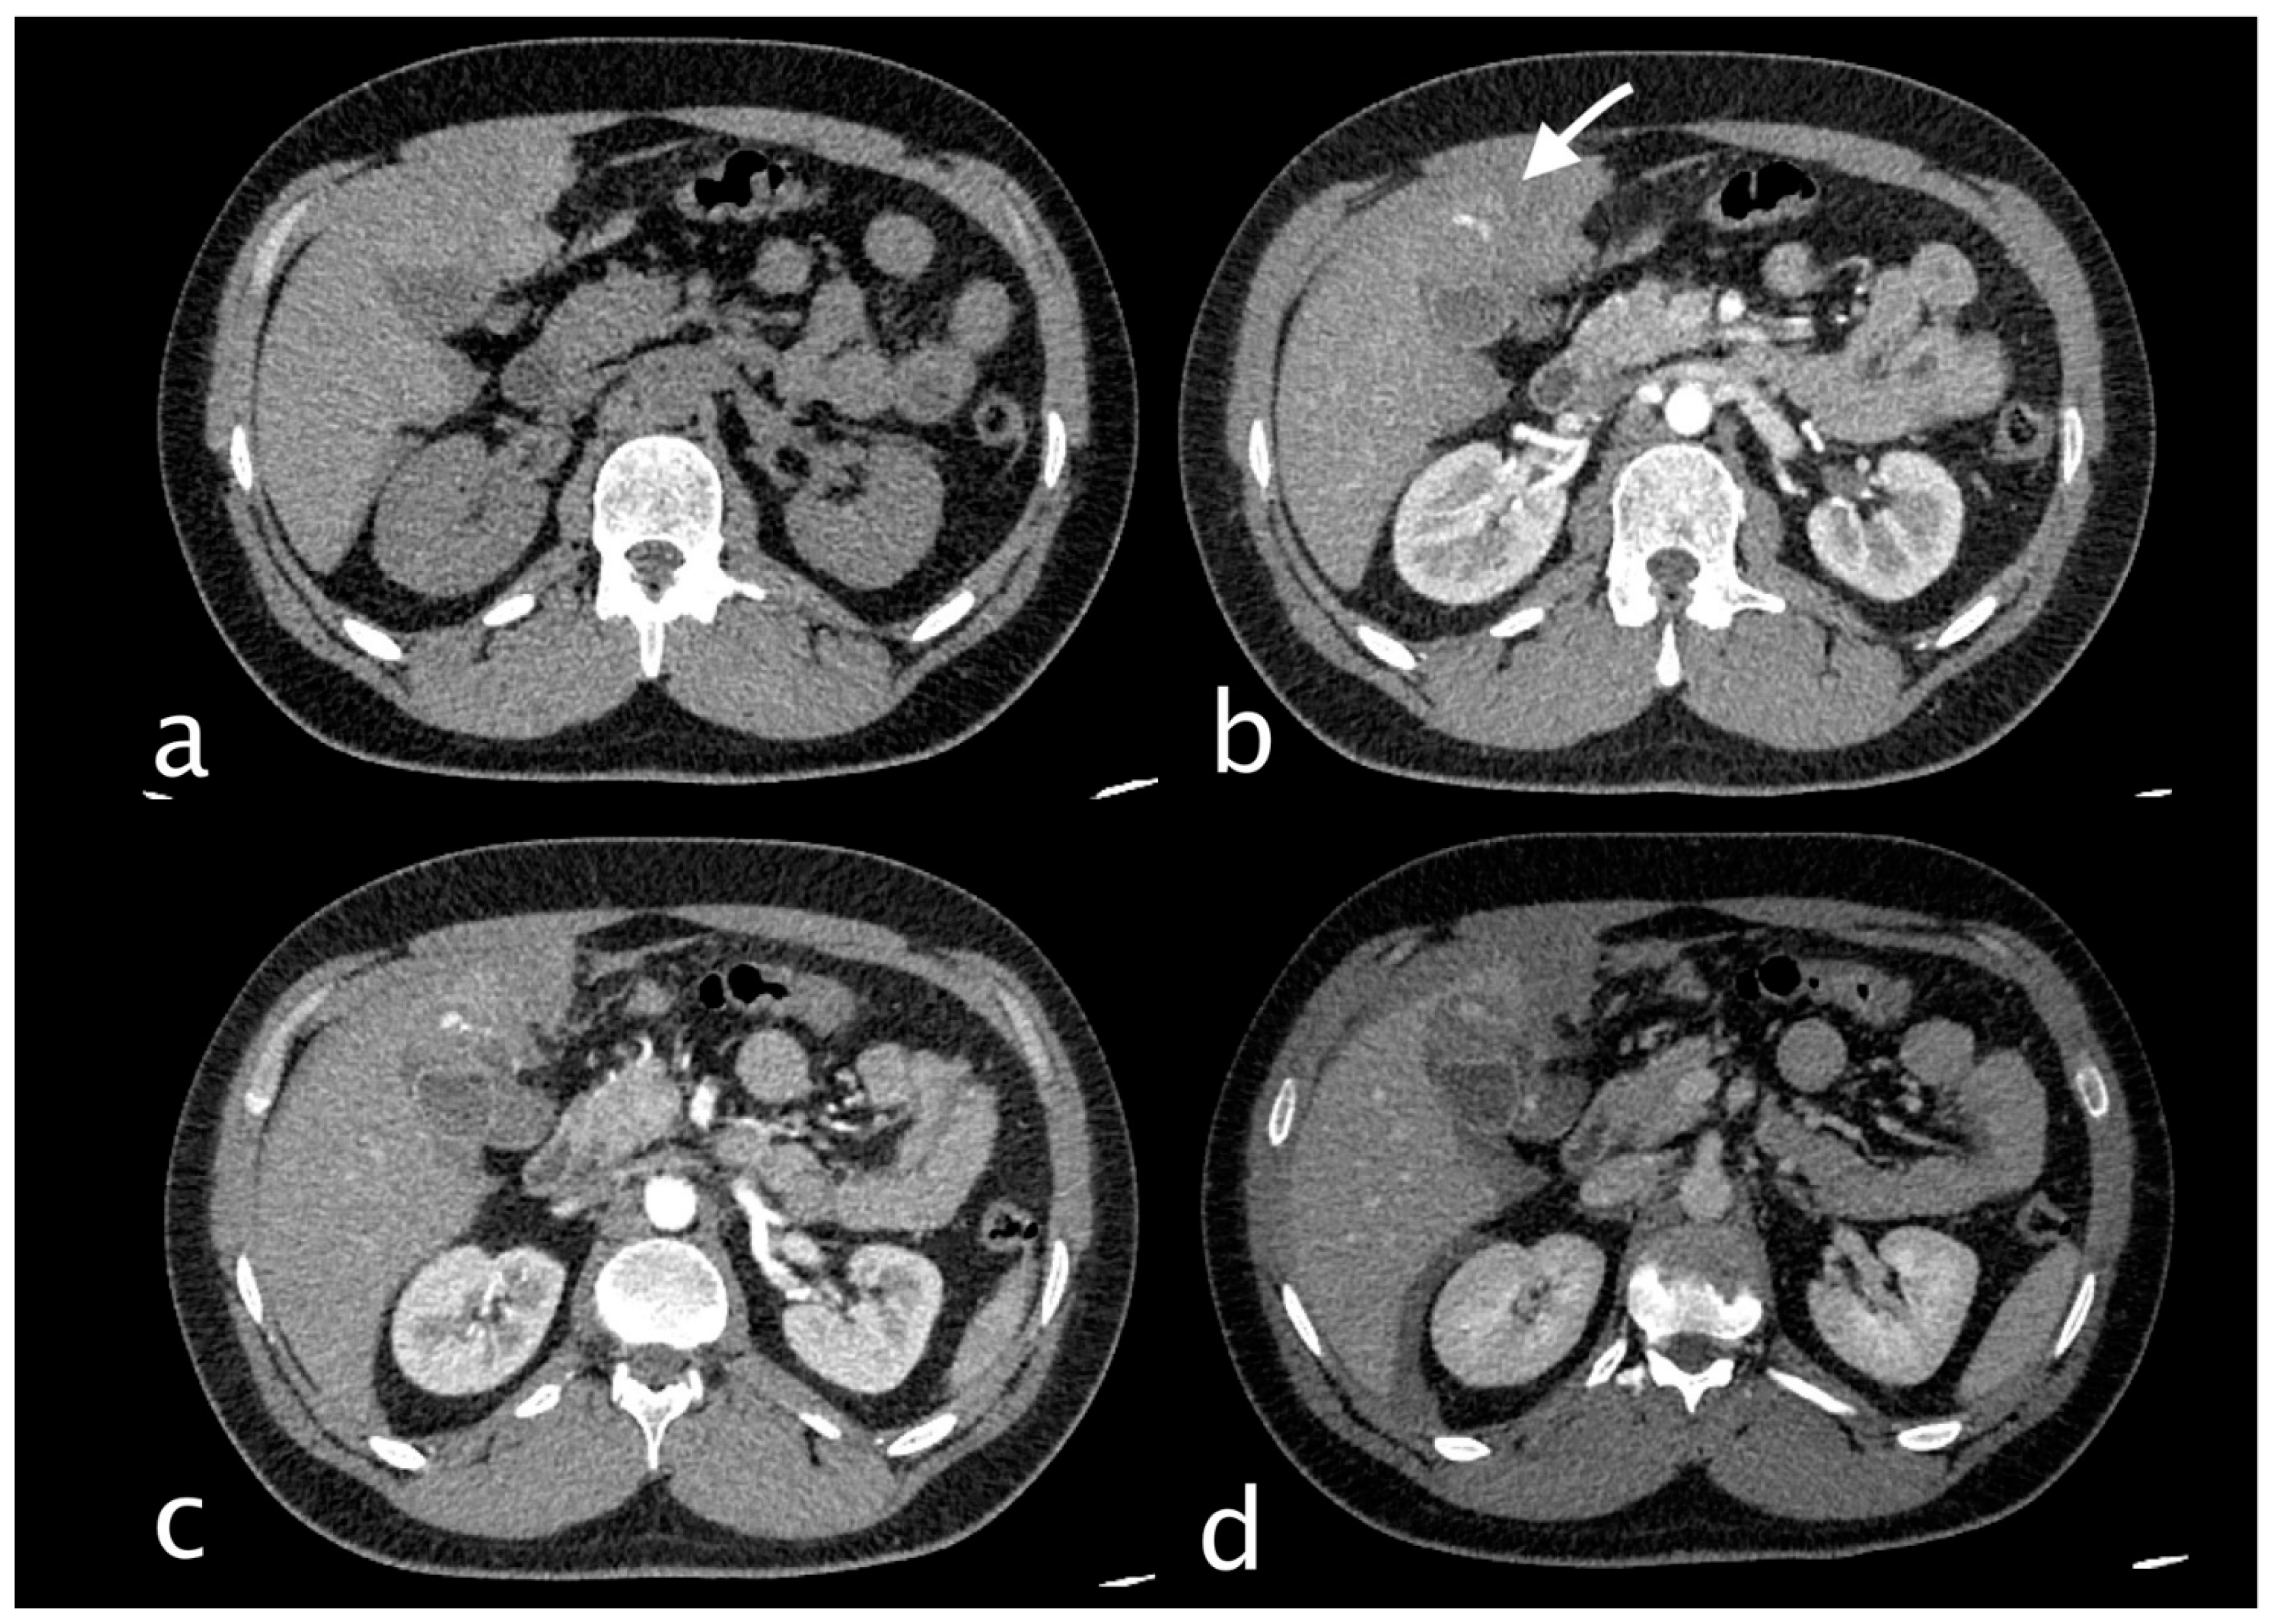

2. Imaging